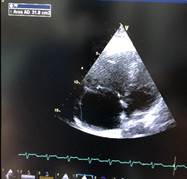

Bajo ese contexto sospechando TEP para confirmar el diagnóstico se realiza Angio-tc de vasos pulmonares (Fig.2 ), que mostro falta de captación de medio de contraste en arteria pulmonar derecha , en cuanto a los exámenes de laboratorio lo más relevante fue troponina 4,7630 u/l , dímero-d 54490,00 ng/ml , ferritina 27300,00 ng/ml. Se procedió a iniciar tratamiento fibrinolítico, que al no contar con r-tpa (alteplase) se usó estreptoquinasa 1.500.000 UI  que fueron administradas de forma intravenosa en una hora, seguida de anticoagulación con enoxaparina, después se evidencio mejoría en la oxigenación y hemodinámica, a las 24 horas se realiza nuevo rastreo ecocardiográfico (Fig. 3) en el cual existe mejoría de función ventricular derecha.

Figura 3. Ecocardiograma Post-fibrinólisis. A función sistólica de VD adecuada TAPSE 1,9. B Cavidades derechas normales.